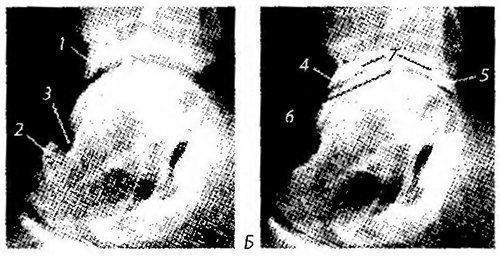

Рис. 344. Рентгенограмма голеностопного сустава с признаками таранно-большеберцового экзостоза и артроза:

А: 7 — большеберцовый экзостоз; 2 — экзостоз бороздки шейки таранной кости; 3 — бороздка шейки таранной кости; Б — проявления артроза: 4-5 — остеофиты переднего и заднего края суставной поверхности эпифиза большеберцовой кости; 6 — сужение и деформация суставной щели; 7— субхондральный склероз